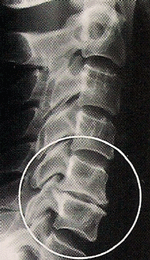

Loss of Normal Curve

Loss of normal curve shows straightening and slight reversal. Nerve irritation, soft tissue inflammation and pain may be present or may occur from minor aggravation.